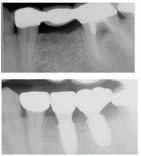

Christopher Chung, DMD

Smile Again Dental Group 818-776-9300

์์น์ง์ ๋ง์น๊ณ ๋์ ๊ฐ๊ธ ํ ๋ฒ ํ๋ฉด, ์

์์ด ํจ์ฌ ๊ฐ์ดํด์ง๊ณ ์์พํ ์ฃ . ์ฌ์ค ๊ฐ๊ธ์ ๊ทธ๋ฅ ์๋ฌด๊ฑฐ๋ ์จ๋ ๋ค ๋น์ทํ ๊ฒ ๊ฐ์ง๋ง, ์ฑ๋ถ๊ณผ ์ฉ๋

์ ๋ฐ๋ผ ๊ฝค ํฐ ์ฐจ์ด๊ฐ ์์ต๋๋ค. ์ด๋ค ๊ฐ๊ธ์ด ์น์ ๊ฑด๊ฐ์ ๋์์ด ๋๋ ์ง, ๋ ์ธ์ ์ด๋ป๊ฒ ์ฌ์ฉํ๋ ๊ฒ ์ข์์ง ์กฐ๊ธ ๋ ์์ธํ ์ ๋ฆฌํด๋ดค์ต๋ ๋ค.

๋จผ์ ๊ฐ์ฅ ํํ ๋ณผ ์ ์๋ ๊ฒ์ด ๋ถ์๊ฐ ๋ค์ด ์๋ ๊ฐ๊ธ์

๋๋ค. ๋ถ์๋

์ถฉ์น๋ฅผ ์๋ฐฉํ๋ ๋ฐ ์์ฃผ ์ค์ํ ์ฑ๋ถ์

๋๋ค.

์น์ ํ๋ฉด์ ๋ ๋จ๋จํ๊ฒ ๋ง๋ค์ด์ฃผ๊ณ , ์ฐ์ ์ํ ์์์ ์ค์ฌ์ฃผ์ฃ . ํนํ

์ถฉ์น๊ฐ ์์ฃผ ์๊ธฐ๊ฑฐ๋ ๋จ ์์์ ์์ฃผ ๋จน๋ ๋ถ๋ค, ์น์๊ฐ ์ฝํ๋ค๊ณ ๋๋ผ

๋ ๋ถ๋ค์๊ฒ ์ ์ฉํฉ๋๋ค. ๋ถ์ ๊ฐ๊ธ์ ํ๋ฃจ์ ํ ๋ฒ, ํนํ ์๊ธฐ ์ ์ฌ์ฉ

ํ๋ฉด ๋ ํจ๊ณผ์ ์ด์์. ๋ฐค์๋ ์นจ์ด ๋ ๋์์ ์ถฉ์น๊ฐ ๋ ์ฝ๊ฒ ์๊ธฐ๊ธฐ

๋๋ฌธ์, ์ ๋ ๋ถ์๊ฐ ์น์๋ฅผ ๋ณดํธํด์ฃผ๋ฉด ํจ์ฌ ๋ ๋ ํ์ฃ .

ํญ๊ท ์ฑ๋ถ

ํ ๊ฐ์ง ์ฃผ์ํ ์ ์ด ์์ด์. ๊ฐ๊ธ์ ๋๋ฌด ์์ฃผ ํ๋ ๊ฑด ์ข์ง ์์ต๋๋ค. ํ๋ฃจ์๋ ๋ช ๋ฒ์ฉ ์ต๊ด์ฒ๋ผ ๊ณ์ ์ฌ์ฉํ๋ฉด, ํด๋ก์ด ์ธ๊ท ๋ฟ ์๋๋ผ ์

์ ์ ํ์ํ ์ข์ ์ธ๊ท ๊น์ง ์ค์ด๋ค ์ ์์ต๋๋ค. ๊ทธ๋ฌ๋ฉด ์คํ๋ ค ๊ตฌ๊ฐ ํ๊ฒฝ

์ด ๋ถ์์ ํด์ง๊ณ , ์

์์ด ๊ฑด์กฐํด์ง ์ ์์ต๋๋ค. ๊ทธ๋์ ์ผ๋ฐ์ ์ผ๋ก๋

ํ๋ฃจ 1~2ํ ์ ๋๋ง ์ฌ์ฉํ๋ฉด ์ถฉ๋ถํฉ๋๋ค.

๊ฐ๊ธ์ ์น์์ ์๋ชธ ๊ฑด๊ฐ์ ์ง์ผ์ฃผ๋ ์ข์ ๋ณด์กฐ ์๋จ์ด์ง๋ง ์ด๋๊น์ง ๋ ๋ณด์กฐ์ผ ๋ฟ, ์นซ์์ง๊ณผ ์น์ค์ ๋์ ํ ์๋ ์์ต๋๋ค.

์์ ์๊ฒ ๋ง๋ ์ ํ์ ๊ณจ๋ผ์ ์ ์ ํ ๋์, ์ ๋นํ ํ์๋ก ์ฌ์ฉํ๋ ๊ฒ

์ด ๊ฐ์ฅ ํ๋ช

ํ ๋ฐฉ๋ฒ์

๊ทธ๋ค์์ ํญ๊ท ์ฑ๋ถ์ด ๋ค์ด ์๋ ๊ฐ๊ธ์

๋๋ค. ๋ํ์ ์ผ๋ก ํด๋ก๋ฅดํฅ์

๋ ์ฑ๋ถ์ด ์๋๋ฐ, ์ด๋ ์๋ชธ ์งํ์ด๋ ์ฌํ ์ผ์ฆ์ด ์์ ๋ ํจ๊ณผ์ ์

๋

๋ค. ์

์ ์ธ๊ท ์ ํ์คํ๊ฒ ์ต์ ํด์ฃผ์ง๋ง, ๋จ์ ๋ ์์ด์. ์ค๋ ์ฐ๋ฉด ์น

์๊ฐ ๋๋ ๊ฒ ์ฐฉ์๋๊ฑฐ๋ ์์ ๋ง์ด ๋ค๋ฅด๊ฒ ๋๊ปด์ง ์ ์์ต๋๋ค. ๊ทธ๋์

์ด๊ฑด ๋ณดํต ์น๊ณผ์์ ์ค์ผ์ผ๋ง์ด๋ ์๋ชธ ์น๋ฃ ํ์ ๋จ๊ธฐ๊ฐ ์ฒ๋ฐฉํ๋ ๊ฒฝ

์ฐ๊ฐ ๋ง์ต๋๋ค. ๋งค์ผ ์ฐ๋ ๋ฐ์ผ๋ฆฌ ๊ฐ๊ธ ์ด๋ผ๊ธฐ๋ณด๋ค๋ ์น๋ฃ์ฉ์ผ๋ก ์๊ฐ ํ์๋ฉด ๋ ๋ง์ต๋๋ค.